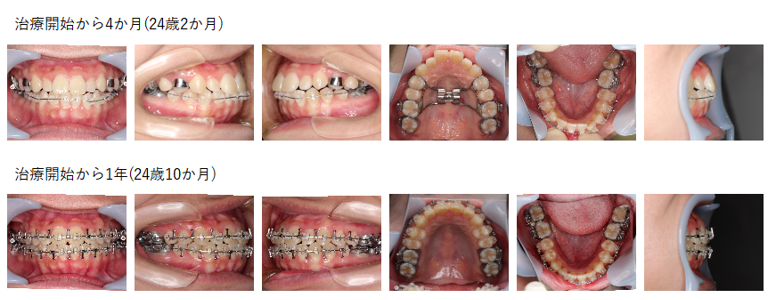

【治療例】初診時年齢:24歳2か月 / 性別:男性 / 主訴:顎のズレ、嚙み合わせのズレ、下の歯が出ている

主訴: 顎のズレ、嚙み合わせのズレ、下の歯が出ている

診断名: 下顎骨の左方偏位を伴ったため左側の交叉咬合を認められた骨格性下顎前突症例

使用した主な装置: マルチブラケット装置、顎間ゴム

抜歯/非抜歯および抜歯部位: 非抜歯

治療期間:4年9か月(2023年2月~は保定期間)

治療回数:41回